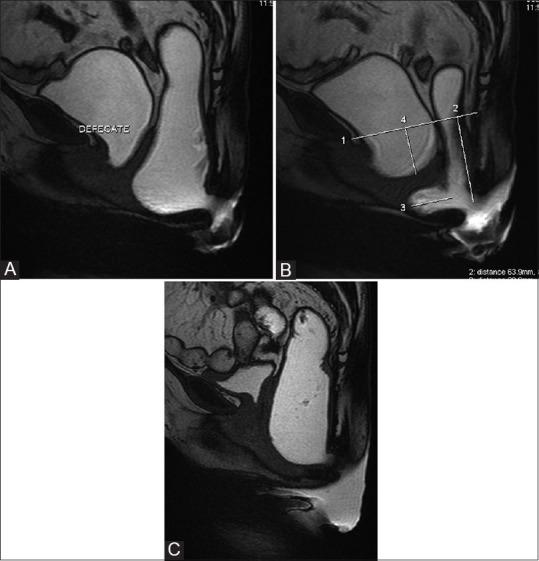

用于排便障碍综合征的磁共振排粪造影

MR defecography for obstructed defecation syndrome.

Patients with obstructed defecation syndrome (ODS) form an important subset of patients with chronic constipation. Evaluation and treatment of these patients has traditionally been difficult. Magnetic resonance defecography (MRD) is a very useful tool for the evaluation of these patients. We evaluated the scans and records of 192 consecutive patients who underwent MRD at our center between January 2011 and January 2012. Abnormal descent, rectoceles, rectorectal intussusceptions, enteroceles, and spastic perineum were observed in a large number of these patients, usually in various combinations. We discuss the technique, its advantages and limitations, and the normal findings and various pathologies.

摘要

排便梗阻综合征(ODS)患者是慢性便秘患者中的一个重要亚组。传统上,对这些患者的评估和治疗一直很困难。磁共振排粪造影(MRD)是评估这些患者的非常有用的工具。我们评估了2011年1月至2012年1月期间在我们中心接受MRD检查的192例连续患者的扫描结果和记录。在这些患者中,大量观察到异常下降、直肠膨出、直肠直肠套叠、肠膨出和会阴痉挛,通常是多种情况并存。我们讨论了该技术、其优点和局限性,以及正常表现和各种病变。